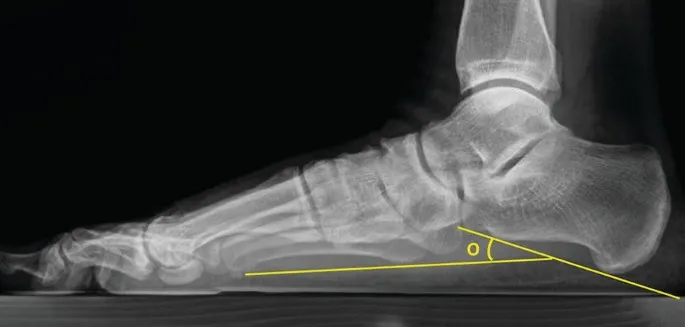

- Radiographic Evaluation (Weight-bearing views):

- Views: AP, Lateral, Hindfoot alignment (e.g., Saltzman).

- Key Angles:

- Meary's Angle (Lat): $angle(talus_long_axis, first_metatarsal_long_axis)$. Normal: 0°. Apex plantar in flatfoot.

- Talonavicular Coverage Angle (AP): Normal: < 7°. ↑ indicates talar subluxation.

- Calcaneal Pitch (Lat): Normal: 20-30°. ↓ in flatfoot (e.g., < 18°).

- Important radiographic angles: Meary's angle, calcaneal pitch, talar declination angle.